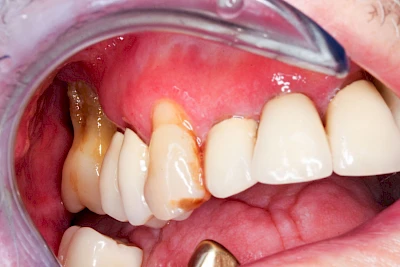

Ist zunächst nur das Zahnfleisch von der Entzündung betroffen, spricht man von Gingivitis. Später, wenn auch der Knochen um die Zähne herum entzündet ist, spricht man von einer Parodontitis. Bei der Parodontitis wird der Knochen nach und nach abgebaut und das Zahnfleisch zieht sich zurück. Die Zahnhälse und Zahnwurzeloberflächen liegen mehr und mehr frei. Die Zähne werden zunehmend lockerer und fallen schließlich aus.

Bei Implantaten – also operativ eingebrachten künstlichen Zahnwurzeln – kann der Körper die Bakterien auch nicht so gut abwehren. Hier spricht man im Fall einer Entzündung von einer Peri-Implantitis, also einer Entzündung um das Implantat herum.